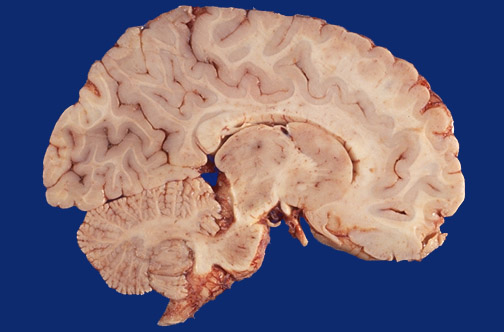

A normal term infant brain is shown in sagittal section near the midline. Identify the following regions in the image above: Caudate - Internal capsule - Cerebral peduncle - Optic tract - Thalamus - Midbrain - Pons - Cerebellar vermis